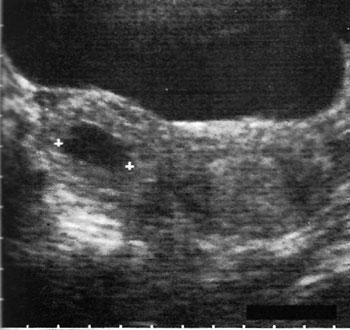

Εικόνα 1. Διακοιλιακός υπερηχογραφικός

έλεγχος έκτοπης κύησης.

Το διακολπικό υπερηχογράφημα είναι ευρέως αποδεκτό ως η καλύτερη επιλογή, έναντι

του διακοιλιακού στη διάγνωση της έκτοπης κύησης.(11) Το διακοιλιακό υπερηχογράφημα

δεν είναι πρακτικό, εξαιτίας της καθυστέρησης πλήρωσης της κύστης και της μη

ικανοποιητικής ποιότητας της εικόνας, ειδικά σε παχύσαρκες γυναίκες. Μερικοί

έχουν καταλήξει ότι η χρήση μόνο του διακολπικού υπερηχογραφήματος αποτελεί

μια πλήρη εξέταση για έκτοπη κύηση, παρόλο που άλλοι έχουν προτείνει τη χρήση

και των δύο τεχνικών με στόχο την αλληλοσυμπλήρωσή τους, καθώς ο διακοιλιακός

υπερηχογραφικός έλεγχος προσδιορίζει μάζες που βρίσκονται ψηλά στην πυελική

κοιλότητα, έξω από την εμβέλεια της ενδοκολπικής κεφαλής.(8-11) Επίσης, το διακολπικό

υπερηχογράφημα απαιτεί λιγότερο χρόνο αναμονής πριν την εξέταση, ενώ παρέχει

μια εικόνα της πυέλου σε υψηλότερη ανάλυση, προσφέροντας πρόσθετες ανατομικές

πληροφορίες.(12-14)

Οι εξαρτηματικές μάζες απεικονίζονται καλύτερα με το διακολπικό υπερηχογράφημα

σε σύγκριση με το διακοιλιακό, οδηγώντας στο συμπέρασμα ότι το διακολπικό υπερηχογράφημα

παρουσιάζει μεγαλύτερη ευαισθησία εντόπισης άμεσων σημείων στην έκτοπη κύηση

(εικόνες 1, 2). Επιπλέον, ακόμη και όταν η διαγνωστική ευαισθησία του διακολπικού